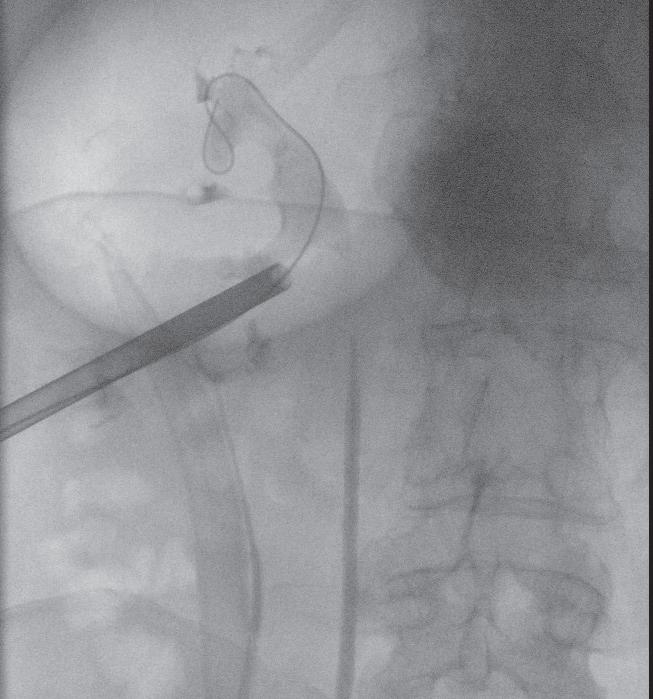

Miniperc 1: Kontrastmitteldarstellung der Kelche und des Nierenbeckens sowie Punktion.

Miniperc 2: Zugang mittels Einschrittdilatators.

Miniperc 3: Finales Bild mit antegrader DJ-Anlage.

Zeigt sich eine ausgeprägte Nephrolithiasis mit einer Größe von über 2 cm, so ist eine PCNL (perkutane Nephrolitholapaxie) empfehlenswert. Diese wird in der Regel mit rigiden Endoskopen durchgeführt und erlebte in den letzten Jahren eine sehr positive Entwicklung. Während in der Vergangenheit klassischerweise Endoskope mit einem Durchmesser von 20 Charrière (Ch.) und Zugangsschäfte von 24-32 Ch. zum Einsatz kamen, hat die zunehmende Verfügbarkeit von miniaturisierten Instrumenten dazu geführt, dass auch größere Steine in der Niere minimalinvasiv bei kürzeren stationären Aufenthalten als früher behandelt werden können. Die PCNL ist deshalb heute kein allgemeingültiger Standard mehr, sondern wird durch die Mini-PCNL, UltraminiPCNL oder Mikro-PCNL verdrängt. Mini-, Ultramini- und Mikro- beziehen sich dabei auf die durchschnittliche Größe der Instrumente. Je kleiner der Durchmesser der Geräte ist, desto geringer das Trauma und somit auch das Blu-

tungsrisiko. Ein kleinerer Durchmesser bedeutet aber auch längere OP-Zeiten. Grundsätzlich wird der Zugang durch die Haut mittels einer entsprechenden Nierenpunktion gelegt (siehe Abbildung, S. 23). Die exakte Positionierung der Punktionsstelle sollte mittels Punktionssonografie und idealerweise kombiniert mit einer Röntgendurchleuchtung erfolgen. Dadurch können die Lage des Konkrements und die Beschaffenheit der Niere besser beurteilt bzw. eingeschätzt werden.9 In der Folge werden die Steine unter Verwendung eines Lasers oder eines Lithoklasten (unter Druckluftwirkung können Steine zerkleinert werden) fragmentiert und die einzelnen Konkremente ausgespült. Dabei zeigten sich bereits früh in der Anwendung dieser Operationstechnik vielversprechende Ergebnisse, sodass die Komplikationsrate mittlerweile überschaubar und die Steinfreiheitsrate hoch ist.10